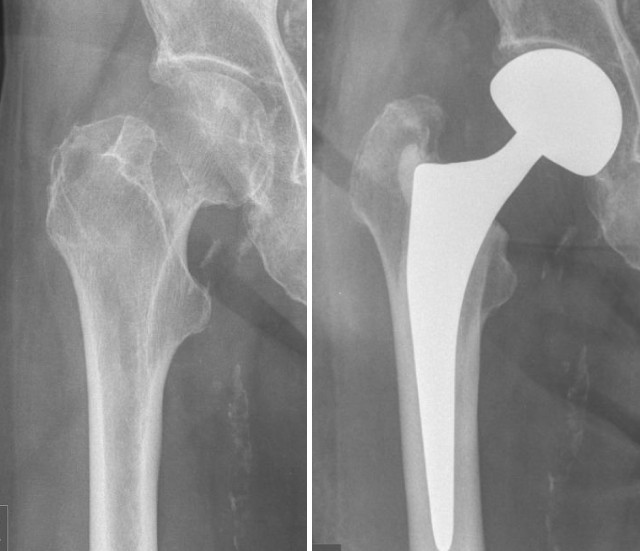

• 5 самых горячих проблем перелома шейки бедра, с которыми сталкиваются ваши коллеги!

5 самых горячих проблем перелома шейки бедра, с которыми сталкиваются ваши коллеги!

2022-09-28

Выбор внутренней фиксации по сравнению с заменой сустава В настоящее время считается, что внутренняя фиксация полым стержнем при переломе шейки бедра имеет преимущества короткого времени операции, небольшой травмы и низкой стоимости, но у большинства пожилых пациентов наблюдается остеопороз, поэтому стабильность